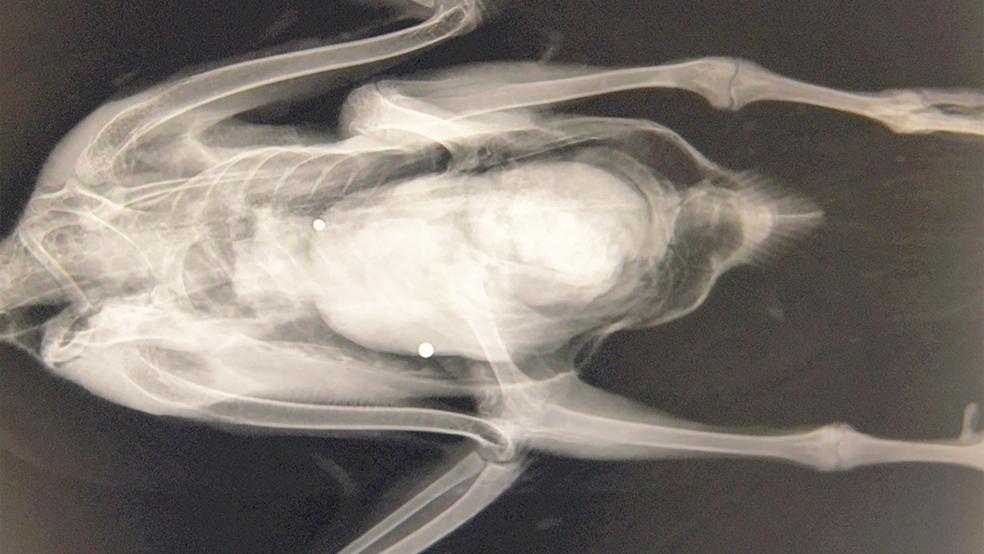

Erneut stehen Jäger im Verdacht, an der Ems geschützte Blässgänse abgeschossen zu haben. »Die Ermittlungen hierzu wurden aufgenommen und dauern an«, teilte Melina Trey, Pressesprecherin der Polizeiinspektion Leer/Emden, auf Anfrage mit. Vogelschützer haben Anzeigen ...